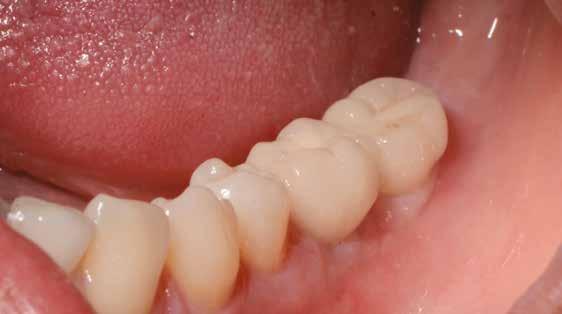

16. ábra: Klinikai kép az implantátumok körüli lágyszövetről a végleges pótlásátadás után. – 17. ábra: Klinikai kép az implantátumok körüli lágyszövetről egy évvel az átadást követően. – 18. ábra: Klinikai kép az implantátumok körüli lágyszövetről két évvel az átadást követően. – 19. ábra: Klinikai kép az implantátumok körüli lágyszövetről öt évvel az átadást követően.

A műtétet követően napi kétszeri, 0,12%-os klórhexidin tartalmú szájvízzel történő öblögetést javasoltunk a páciensnek, két héten keresztül. Gyulladáscsökkentésre 8 óránként 400 mg Ibuprofént javasoltunk, három napon keresztül. A páciens elmondása szerint sem fájdalmat, sem különösebb diszkomfortot nem tapasztalt. Ezt követően, további 4 héten keresztül, 0,2%-os klórhexidin tartalmú szájvízzel történő öblögetést javasoltunk a betegnek és instruáltuk, hogy lehetőleg ne mossa fogkefével az érintett területet. A varratokat egy héttel később távolítottuk el. A donor és a recipiens terület – 10 nappal a műtétet követően – kiválóan gyógyult (15–16. ábra). Az ezt követő kontrollokat a következő időpontokban ejtettük meg: kettő, illetve négy héttel a műtét után, majd három, hat és tizenkét hónappal később, ezt követően pedig félévente (17–20. ábra). Minden kontroll alkalmával professzionális fenntartó kezelést végeztünk a területen.

ságát egy ISO #15-ös endodonciai fájllal mértük 2 mm-re a marginális ínyszéltől meziálisan, disztálisan, illetve az implantátum tengelyében (mint referenciapont). A keratinizált íny szélességét parodontológiai szondával regisztráltuk a kiindulás és a kontrollvizsgálatok alatt. A méréseket elvégeztük a műtét előtt, közvetlenül utána, 4 héttel később, majd egy és két év elteltével. A klinikai paramétereket (keratinizált íny szélessége, lágyszövet volumen és recessziófedés) regisztráltunk a kiinduláskor és az utánkövetés időpontjai alatt. Kiinduláskor a feszes íny szélessége minimális volt (1 mm). A keratinizált ínyszélesség terén négy hétnél 2 mm-t sikerült nyerni, egy évnél 3 mm-t és öt év alatt 5 mm-t. A recessziót 100%-osan sikerült fedni 4 hét után, és ez nem változott sem egy év, sem öt év után.

A páciens mobilis implantátum körüli lágyszövettel rendelkezett, a keratinizált íny szélessége kevesebb volt, mint 1 mm és a nyálkahártya vastagsága nem érte el a 2 mm-t. Az ínyszél az implantátum platform vonalában volt. Az alábbi műtéti technikával jelentős javulást sikerült elérnünk az implantátum körüli lágyszövetek minőségében és a nem elmozduló keratinizált szövet szélesedett 4 mm-rel. A Kígyótechnikánál alkalmazott elforgatott lebeny a szabad keratinizált íny lebeny előnyeivel növeli a nem elmozduló nyálkahártya szélességét az implantátum körül. Biztosítja továbbá a jó vérellátást és a nyeles lebeny stabilitását, ami kisebb mértékű zsugorodást eredményez, mint egy szabad lágyszövet lebenyátültetésnél (29).

Az implantátum körüli lágyszövet defektusok teljes rehabilitációját sikeresen elérhetjük egy második műtéttel elvégzett lágyszövet augmentációval. A javasolt módosított, nyelezett Kígyó lebeny technika jelentősen javított az implantátum körüli lágyszöveteken, mind szélesség, mind vastagság tekintetében egy, kettő és öt évvel a műtét után is egyaránt tartós maradt az eredmény. Az előnyei a következők: nincs szükség második sebre (távoli donorterületre), jobb a vaszkularizáció, nincs nekróziskockázat, gyorsabb a gyógyulás mind a donor, mind a recipiens területen, nincs nagyobb fájdalom vagy diszkomfort. Hosszú távú utánkövetéses, randomizált kontrolltanulmányokra van szükség ahhoz, hogy megállapítsuk, hogy valóban egy tartós, megbízható módszerről van szó.